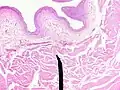

When viewed under a microscope the bladder can be seen to have an inner lining (called epithelium), three layers of muscle fibres, and an outer adventitia.[6]

The inner wall of the bladder is called urothelium, a type of transitional epithelium formed by three to six layers of cells; the cells may become more cuboidal or flatter depending on whether the bladder is empty or full.[6] Additionally, these are lined with a mucous membrane consisting of a surface glycocalyx that protects the cells beneath it from urine.[12] The epithelium lies on a thin basement membrane, and a lamina propria.[6] The mucosal lining also offers a urothelial barrier against the passing of infections.[13]

These layers are surrounded by three layers of muscle fibres arranged as an inner layer of fibres orientated longitudinally, a middle layer of circular fibres, and an outermost layer of longitudinal fibres; these form the detrusor muscle, which can be seen with the naked eye.[6]

The outside of the bladder is protected by a serous membrane called adventitia.[6][14]

Vertical section of bladder wall

Layers of the bladder wall and cross-section of the detrusor muscle

Anatomy of the male bladder, showing transitional epithelium and part of the wall in a histological cut-out